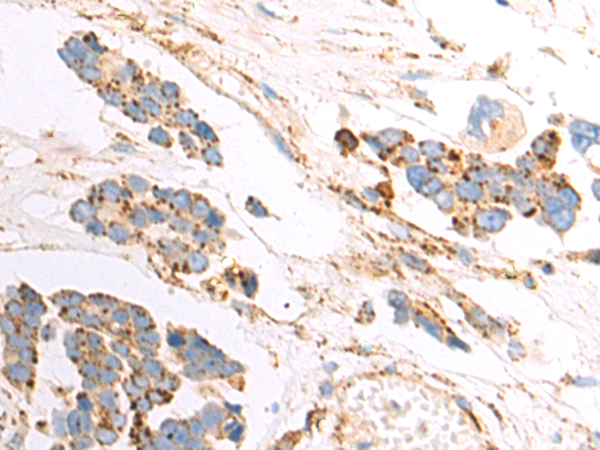

分类: 科研抗体货号: P00239别名: CTSU; CATL2; CTSL2应用: WB,IHC反应种属: Human, Mouse